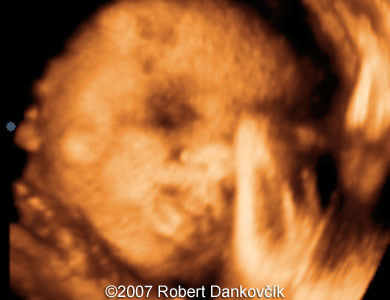

Images 7: 3D image - normal fetal face.